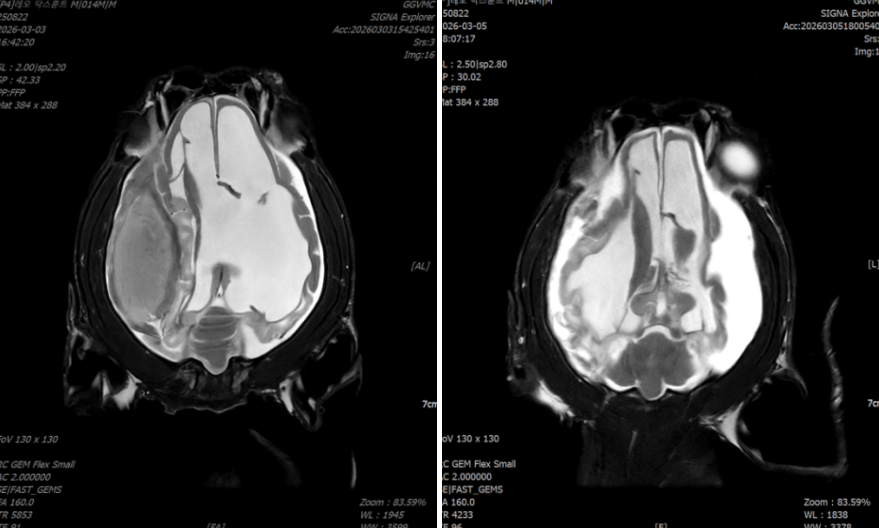

- MRI 검사에서는 두개강 내 혈종과 함께 뇌실 확장이 확인되었습니다.

<좌: 수술 전, 우: 수술 후>